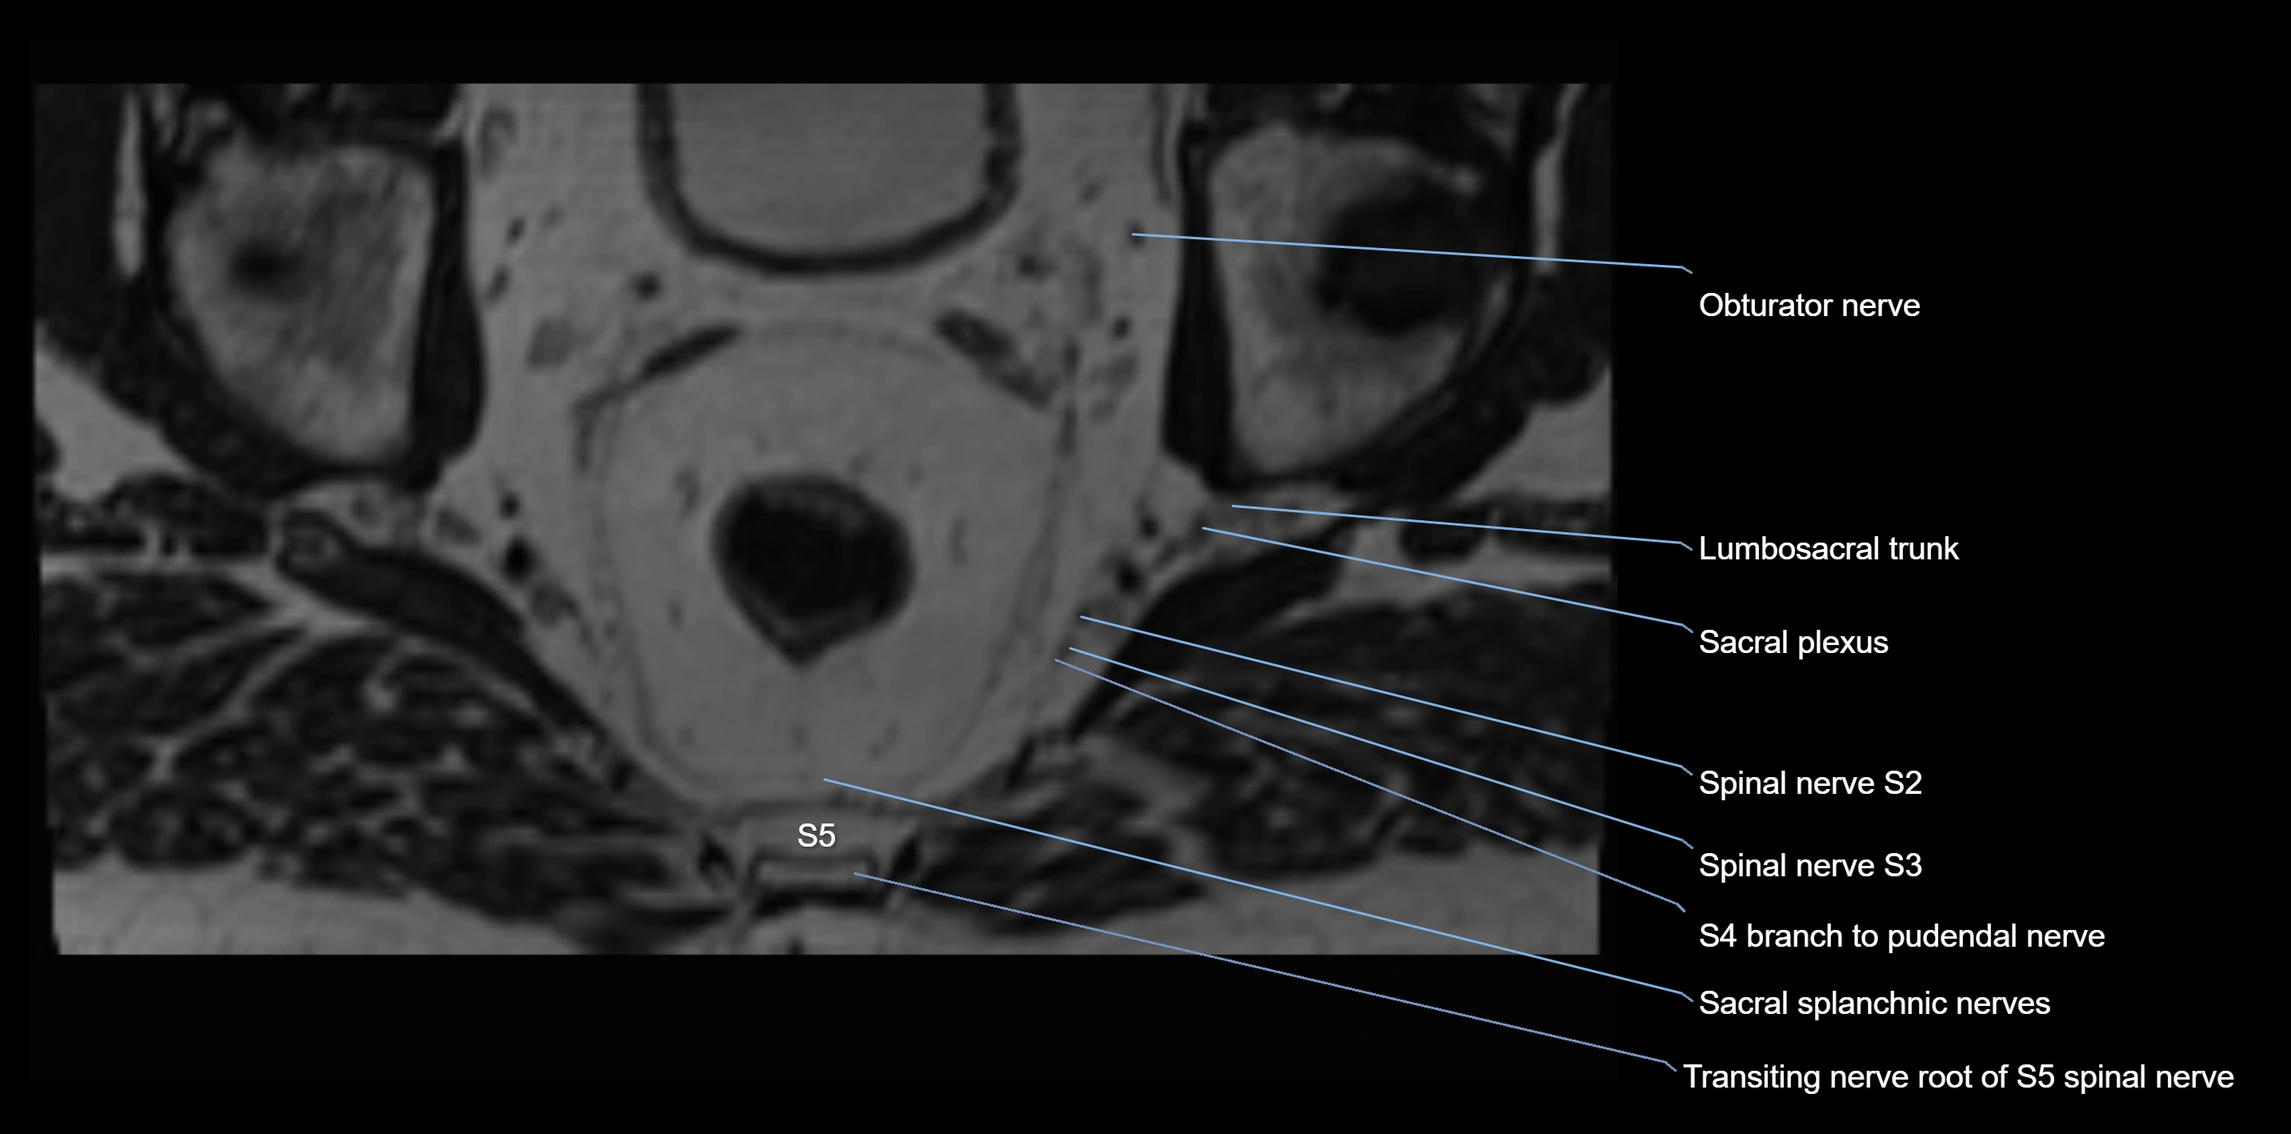

MRI image

image